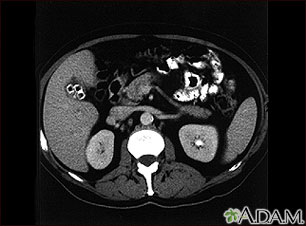

Cholecystolithiasis. CT scan of the upper abdomen showing multiple gallstones.